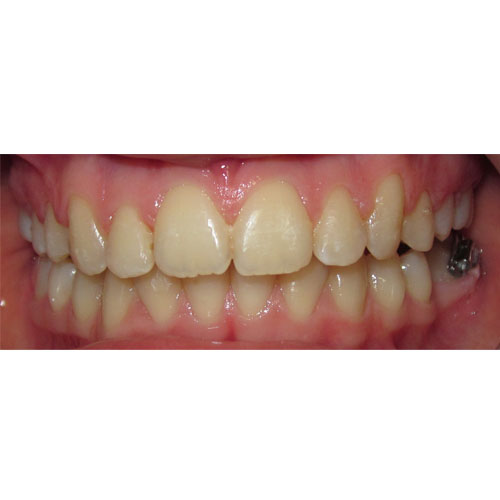

Nasze rezultaty